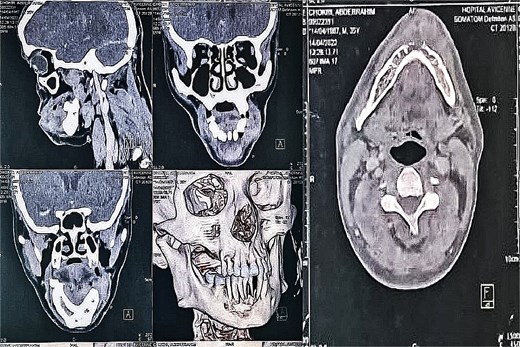

Facial CT, including 3D reconstructions, showed aggressive tumor behavior with mandibular cortical lysis at the symphysis, suggesting local invasion (Fig. 2).

CT scan of the facial mass with axial, coronal, and sagittal slices, as well as 3D reconstructions, showing the tumor and its aggressiveness with cortical lysis at the symphysis.